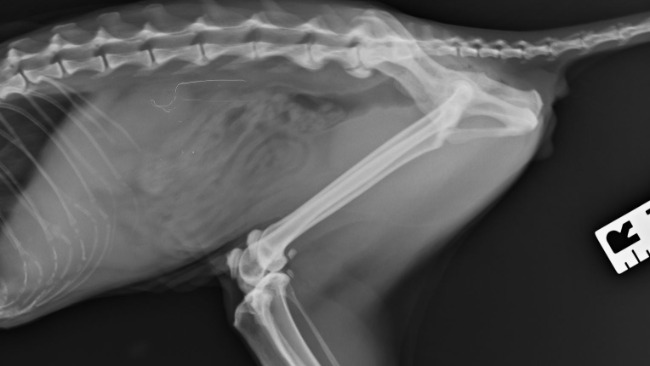

Niunia jest rezolutną kotką, pełną życia i radości w oczkach. Uwielbiała sie bawić z innymi domownikami i towarzyszącymi jej innymi kotami domowymi. Niestety od jakiegoś czasu jej stan zdrowia mocno się pogorszył. Straciła ochote na zabawę, przeszła zabieg usuwania kamieni z pęcherza - ratujemy naszą kicie na wszystkie możliwe sposoby. Po zabiegu odzyskała chęć na zabawę, zaczęła się wspinać, wypróżnianie nie było już takie trudne dla niej. Jednak z dnia na dzień jej stan zdrowia się pogorszył, a po świętach Bożego Narodzenia doprowadził do tego, że kicia nie jest w stanie samodzielnie chodzić.. Nagle kicia przestała chodzić. Po konsultacji weterynaryjnej wiem, że tak naprawde ból kręgosłupa nie pozwala jej normalnie korzystać z życia. Niunia ma stwierdzone zwyrodnienie kręgosłupa.. potrzebny jest rezonans magnetyczny, który jest mega kosztowny i być może po tym badaniu zostałaby zakwalifikowana na operacje kręgosłupa.. 😔💔

Od kilku lat kicia zmaga się z chorobą nerek, ale mimo doskwierających problemów moczowych jej wyniki badań są bardzo zadowalające. Nie można jednak tego powiedzieć o jej kręgosłupie. Kotka ma 10 lat więc tak naprawdę ma przed sobą jeszcze kilka lat życia, niestety bez kosztownego zabiegu czeka ją wózek inwalidzki..

Dziś nie jest w stanie zrobić nawet dwóch kocich kroków, nie jest w stanie usiąść, ponieważ od razu się przewraca. Wchodzenie na wysokość i korzystanie z kuwety jest nie wykonalne bez przewrócenia się. Oprócz tego towarzyszy jej zanik mięśni skokowych. Próbujemy tego uniknąć masażami i rehabilitacją domową.